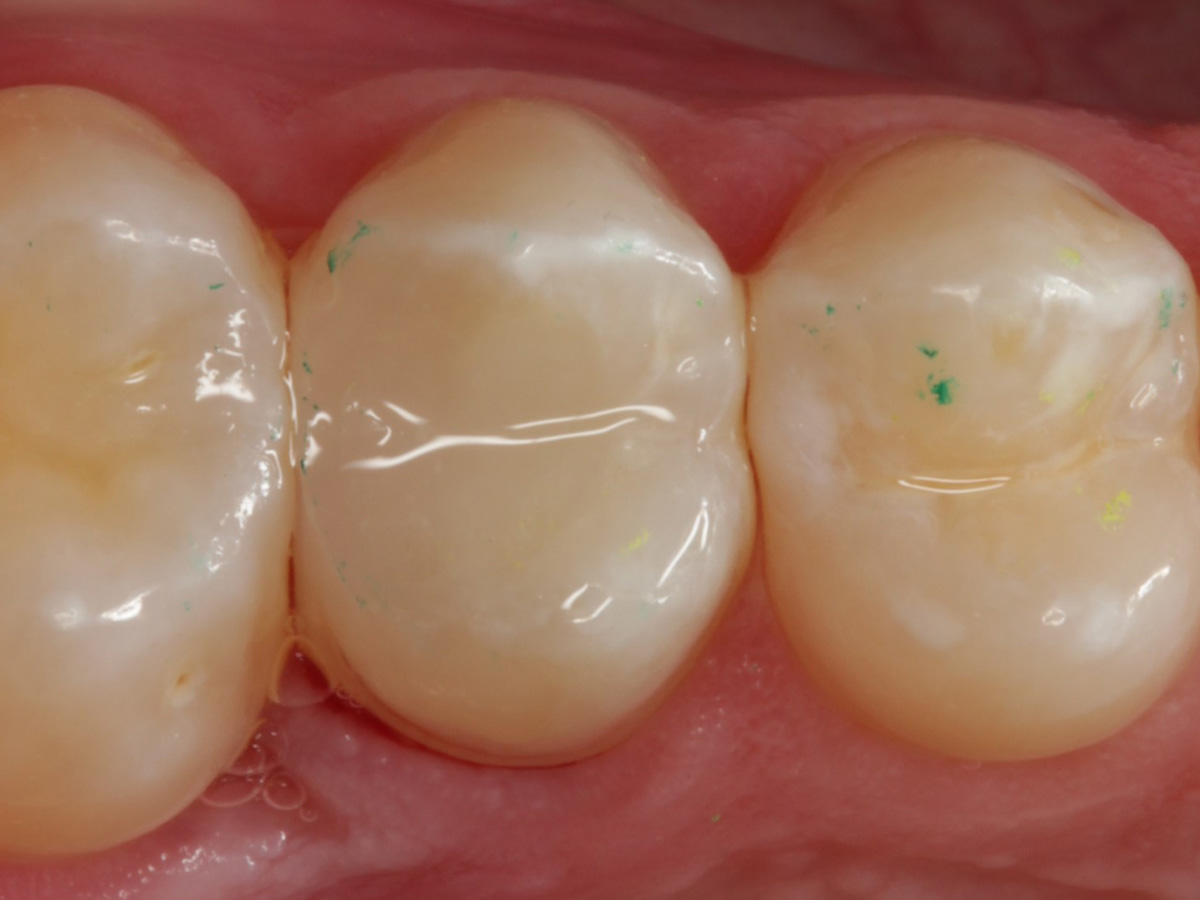

Abbildung 28

Kompositrestauration nach „Schachtverschluß“; keine Krone geplant